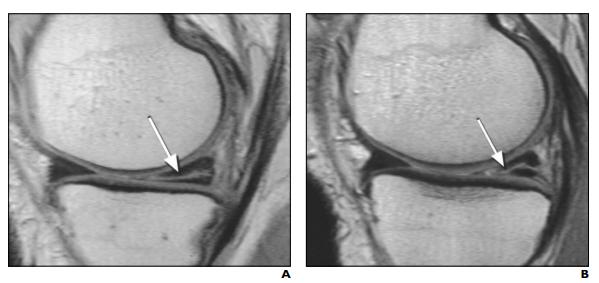

A:患侧腿半月板异常;B(同一人)健侧腿半月板异常

这57个人里面,有36个人的磁共振居然发现,他们的另外一条完全正常没有一点点不舒服的膝盖,居然片子上也有半月板撕裂。 36/57,这个比例高于50%啊。。。

结果发现,100个人里有57个的磁共振,的确发现疼的那条腿的半月板有撕裂。而更有意思的是: